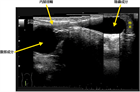

1. 無痛性(無症候性)陰嚢腫大は、まずエコー検査で陰嚢水瘤を確認する。

1. エコー検査で陰嚢水瘤であれば、精巣の位置、鼠径部での精巣鞘膜(鞘状突起)の開存、Abdominoscrotal hydroceleの腹腔内成分がないか確認する。